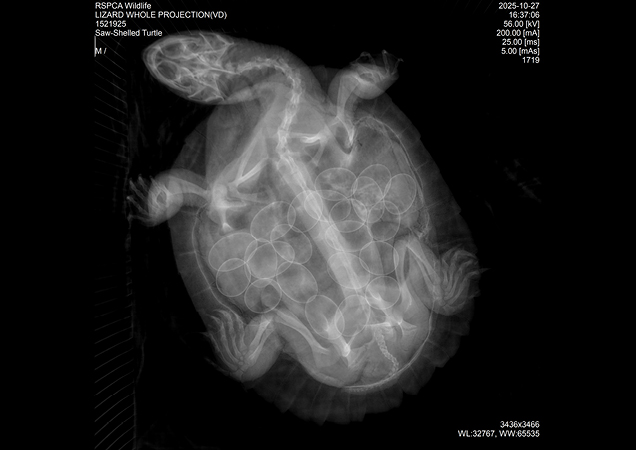

A radiograph revealed that this old mother was carrying 22 eggs!

Late last year, our RSPCA Rescue Team attended a call about a saw shelled river turtle that had been hit by a car. Arriving at our RSPCA Wildlife Hospital in Brisbane, the turtle was no spring chicken - likely around 50 years of age!

Named Mira, this poor turtle’s injuries were severe. She had fractures to both her top and bottom shell. Painful and complex with a long road to recovery. But that wasn’t all…